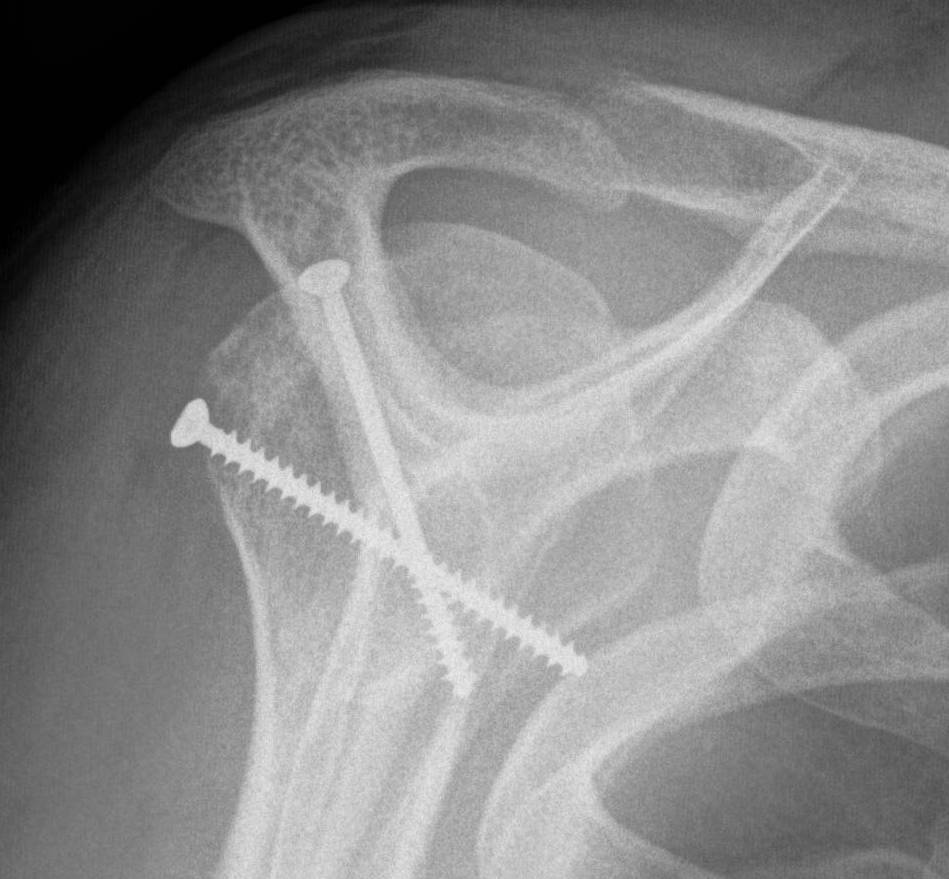

Humeral head allograft

Indications

Large Hill Sachs defect

Technique